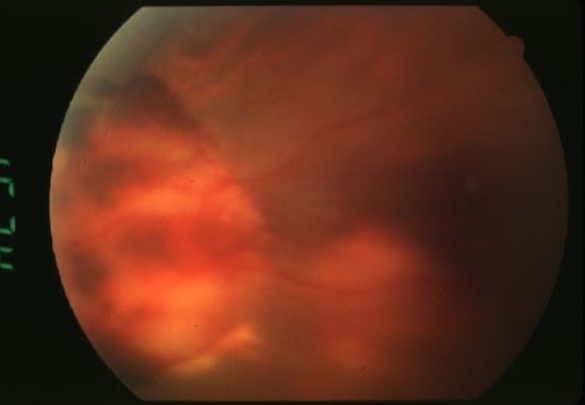

metastatic carcinoma

metastatic carcinoma

metastatic carcinoma

metastatic carcinoma

metastatic carcinoma

metastatic carcinoma

metastatic carcinoma

metastatic carcinoma

metastatic carcinoma

metastatic carcinoma of choroid

features:

cream, yellow, light brown

flat or slightly elevated mottled pigment clumping on surface

extensive exudative RD

maybe multifocal or bilateral